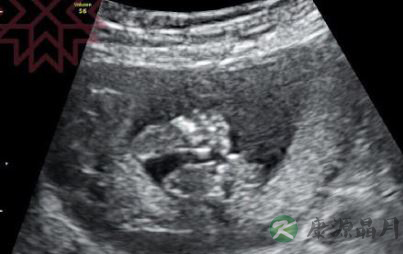

1月26日下午,伊能静在微博晒出做产检时二胎B超照,并配文称“产检……可爱的小手小脚,脚趾手趾都看的到”,喜悦之情溢于言表。

近日伊能静公布怀孕喜讯,她曾在微博发长文讲述自己的艰辛备孕过程,也时常与网友分享怀孕期间的感受。26日她晒出二胎B超照,照片中宝宝的小手小脚轮廓已经可以辨别,连手指脚趾都能看得见。